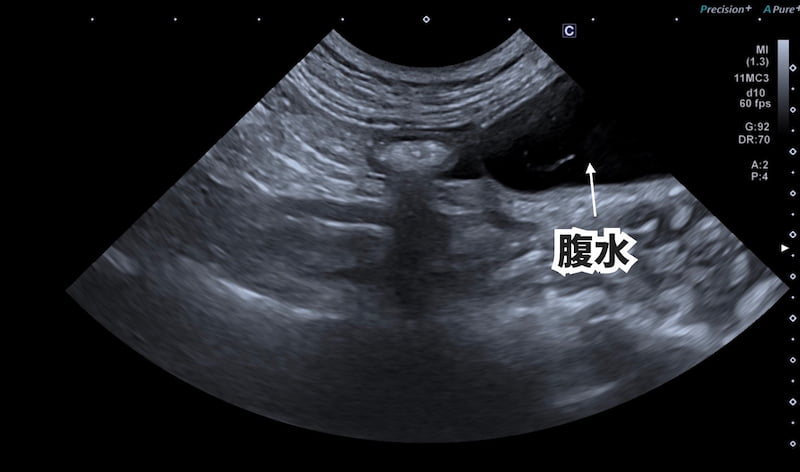

お腹が張っていたので、X線検査と超音波検査を実施したところ、お腹に水が溜まっていました。

腹水を抜いてみると、薄い黄色の少し粘性のある液体でした。